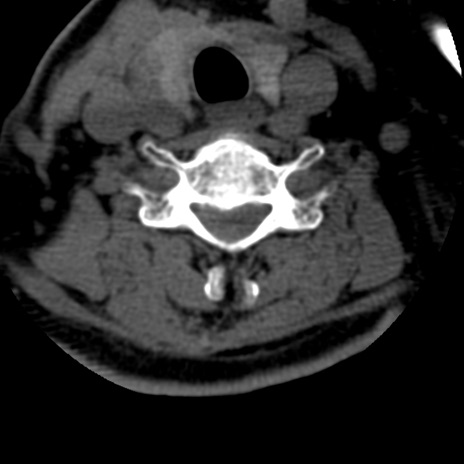

症例50 頚椎CT(横断像)

異常所見と診断は?

頚椎CT